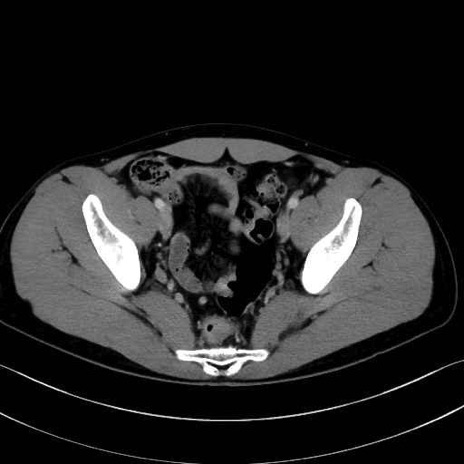

精嚢(seminal vesicle)のCT画像における解剖

症例

【症例】20歳代 男性 スクリーニング